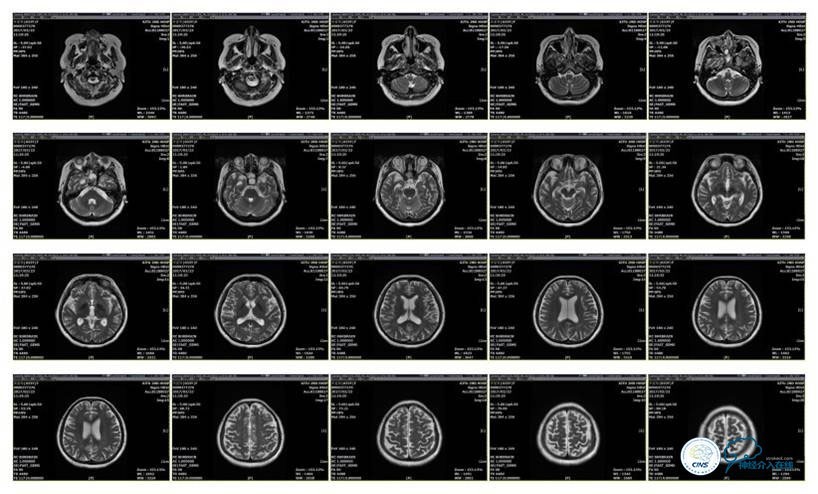

病史:患者于1年余前,因头部外伤在外院行头颅CT提示:未见异常。约3月后患者出现头痛、发作性意识丧失,在当地医院行头颅CT及MRI提示:未见明显异常。诊断为外伤性癫痫,予以对症治疗,未见明显好转。6月余前,无明显诱因出现鼻腔漏液,予以保守治疗,此后鼻腔间断漏液,漏液后头痛缓解。13天前因高热、恶心、呕吐在外院诊断为颅内感染(肺炎链球菌),予以抗炎等对症治疗2周后鼻漏停止,体温正常,CSF常规、生化正常,但头痛仍未缓解,转入我院神经内科治疗。反复腰穿颅内压450-500mmH2O左右,脑脊液常规及生化均正常。颅脑CT及MRI、MRV提示:左侧顶叶硬膜下血肿,鼻窦炎、乳突炎、左侧横窦、乙状窦闭塞、右侧横窦、乙状窦狭窄。予以华法林抗凝治疗2周,维持INR2-3,患者头痛仍无明显缓解,颅内压无下降,转入我科。

头颅CT

MRI T1

MRI T2

MRV

诊断:1、右侧横窦、乙状窦狭窄;2、硬膜下血肿(左侧顶);3、继发性癫痫;4、脑脊液鼻漏;5、颅内感染;6、乳突炎;7、鼻窦炎。

病理过程推理:首先是乳突炎—诱发左侧横窦乙状窦血栓最终闭塞,右侧横窦乙状窦狭窄—导致颅内高压,造成头痛及癫痫—持续颅内高压—皮层静脉回流受阻导致自发性硬膜下血肿及自发性脑脊液鼻漏—颅内感染。